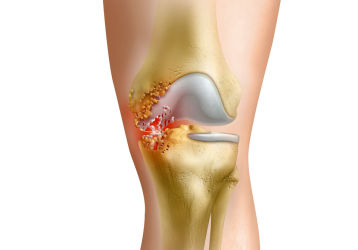

Артрит — это сложная патология, которая имеет системный характер. Это ревматическое воспаление соединительной ткани, которое в основном поражает мелкие сочленения. Ревматоидный артрит имеет осложненный патогенез. То есть его дальнейшее развитие способствует деформации суставов. Восстановить их медикаментозным путем уже практически невозможно.

Точные причины болезни установить так и не удалось, однако, доподлинно известно, что данная патология приводит к инвалидности в 70% случаев. Несвоевременное лечение — прямой путь к оперативному вмешательству и серьезным осложнениям. Подвержены такому нарушению здоровья практически все люди на земном шаре. При этом болезнь начинает развиваться в 40—50 лет. Диагностируется артрит чаще у женщин.

Правильная терапия может замедлить прогресс патологии. Кроме того, лечение улучшает качество жизни, так как устраняет постоянную боль, восстанавливает подвижность. Существует много способов лечения заболевания, о которых нужно знать, чтобы продлить здоровье своих суставов. Наш портал ответит на все вопросы, связанные с данным заболеванием.